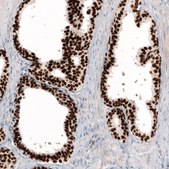

immunohistochemistry: 1:5000- 1:10000

The Human Protein Atlas project can be subdivided into three efforts: Human Tissue Atlas, Cancer Atlas, and Human Cell Atlas. The antibodies that have been generated in support of the Tissue and Cancer Atlas projects have been tested by immunohistochemistry against hundreds of normal and disease tissues and through the recent efforts of the Human Cell Atlas project, many have been characterized by immunofluorescence to map the human proteome not only at the tissue level but now at the subcellular level. These images and the collection of this vast data set can be viewed on the Human Protein Atlas (HPA) site by clicking on the Image Gallery link. We also provide Prestige Antibodies® protocols and other useful information.

• IHC tissue array of 44 normal human tissues and 20 of the most common cancer type tissues.